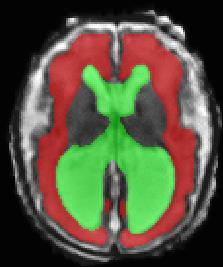

Limiting failures of machine learning systems is of paramount importance for safety-critical applications. In order to improve the robustness of machine learning systems, Distributionally Robust Optimization (DRO) has been proposed as a generalization of Empirical Risk Minimization (ERM). However, its use in deep learning has been severely restricted due to the relative inefficiency of the optimizers available for DRO in comparison to the wide-spread variants of Stochastic Gradient Descent (SGD) optimizers for ERM. We propose SGD with hardness weighted sampling, a principled and efficient optimization method for DRO in machine learning that is particularly suited in the context of deep learning. Similar to a hard example mining strategy in practice, the proposed algorithm is straightforward to implement and computationally as efficient as SGD-based optimizers used for deep learning, requiring minimal overhead computation. In contrast to typical ad hoc hard mining approaches, we prove the convergence of our DRO algorithm for over-parameterized deep learning networks with ReLU activation and a finite number of layers and parameters. Our experiments on fetal brain 3D MRI segmentation and brain tumor segmentation in MRI demonstrate the feasibility and the usefulness of our approach. Using our hardness weighted sampling for training a state-of-the-art deep learning pipeline leads to improved robustness to anatomical variabilities in automatic fetal brain 3D MRI segmentation using deep learning and to improved robustness to the image protocol variations in brain tumor segmentation. Our code is available at https://github.com/LucasFidon/HardnessWeightedSampler.